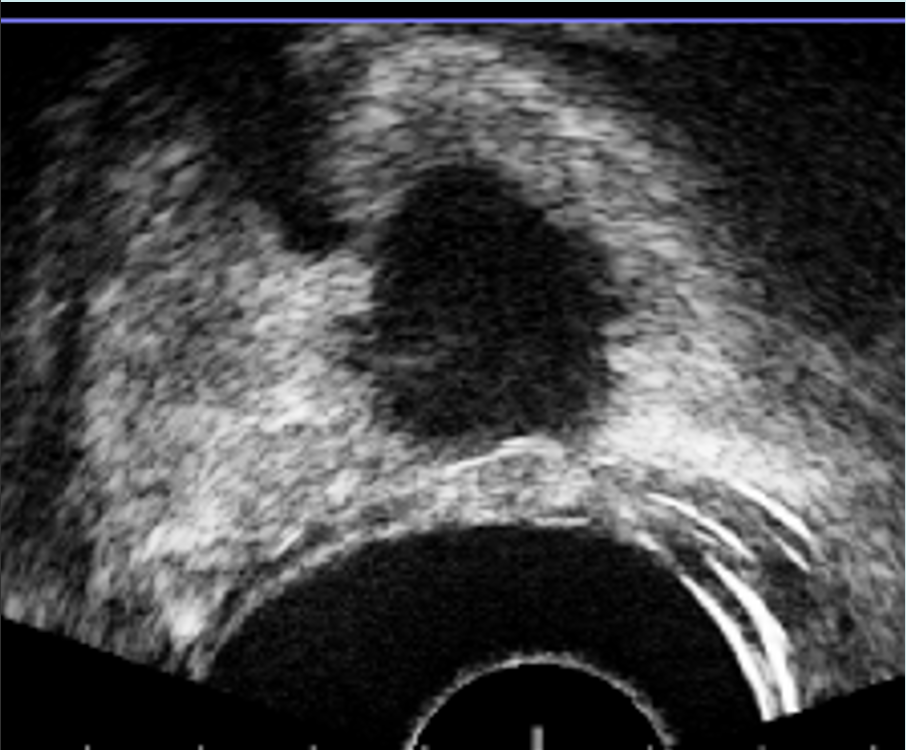

La próstata se escanea con la sonda de US. El operador define los contornos de la próstata y delinea las lesiones sospechosas a tratar en las imágenes de Resonancia. Los límites de la próstata se definen en la imagen en tiempo real de la próstata obtenida con la sonda trans-rectal del dispositivo. El software ejecuta automáticamente una “fusión elástica” de los dos volúmenes definidos, lo que conduce a una combinación tridimensional (3D) perfecta del volumen de RM con el volumen de la próstata en US. La misma fusión 3D se aplica al área sospechosa previamente identificada en la resonancia magnética y/o Biopsia por fusión que, por lo tanto, se puede identificar correctamente en la imagen en vivo de US. (Figura 3-4).

Al final del tratamiento, el sistema le permite al médico evaluar los resultados finales del proceso realizando US con contraste (CEUS) (Figura 5). La imagen se puede comparar con la resonancia magnética inicial para verificar la correcta ablación de la lesión cancerosa.